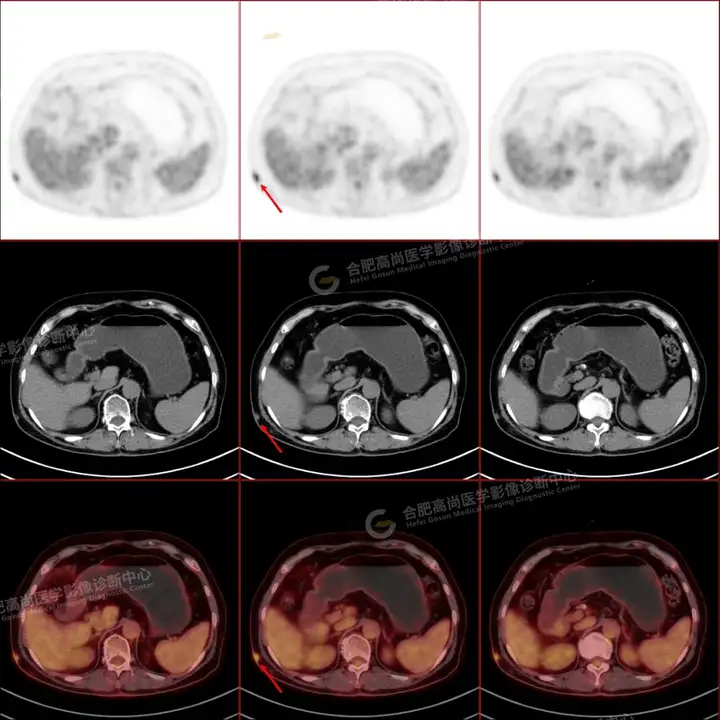

PETCT检查所示:图1、3-17全身多处(双上臂、胸背部、左侧乳腺、左侧腰部、腹壁、双侧臀部及双侧大腿)皮肤下结节及肿块样软组织密度灶,FDG代谢不同程度增高,双侧颈部、左侧锁骨区、纵隔内(1区)及双侧腋窝多发肿大淋巴结,FDG代谢明显增高,符合皮肤来源淋巴瘤。